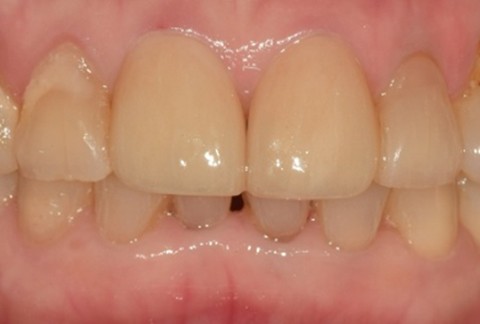

임플란트-보철-시-기성-어버트먼트가-아닌-맞춤-지대주-사용-보철-파절-위험-방지-음식물-끼임-방지-주위염-방지-맞춤-지대주는-환자의-구강환경에-맞는-교합을-구현할-수-있고-앞니-보철시-더욱-심미적으로-제작이-가능합니다

임플란트-전후사진